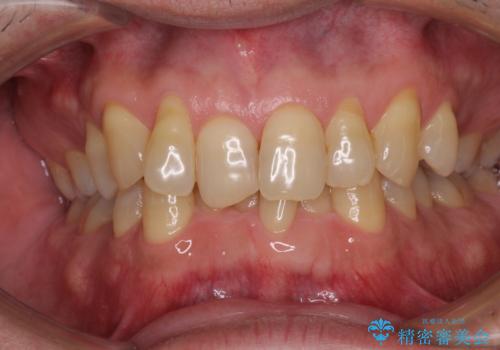

- 強い咬合力による歯肉退縮により、歯の根の黄色い色が見えてしまうことを気にされて来院された患者様です。

ディープバイトで咬合力が強く、該当歯に負担のかかりやすい咬み合わせであったため、歯肉退縮が起こりやすいと判断された患者様でした。

根面被覆を達成するとともに、歯肉の厚みを増すことで、今後歯肉退縮を起こしにくくするよう配慮した処置としました。